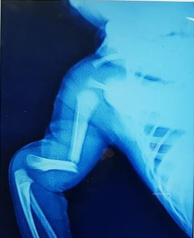

Fractures due to birth trauma

Before

Humerus shaft fracture at birth

After

Managed conservatively with vulpeau's sling